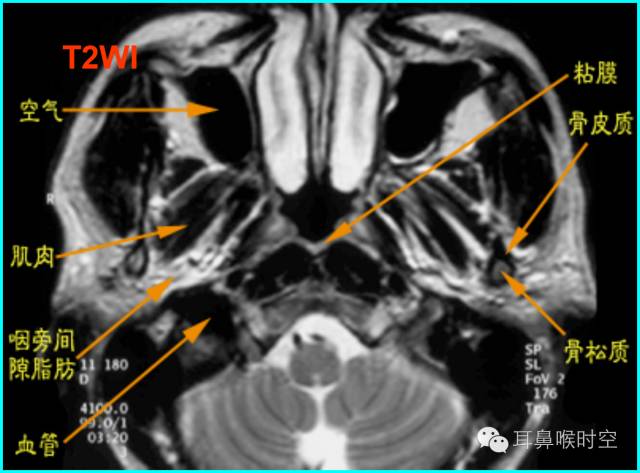

咽部正常CT表现

(1)鼻咽腔层面:

(2)口咽腔层面

(3)喉咽腔层面:

MRI

MRI表现:

多方位检查

有利于显示肥大的腺样体

呈等T1、长T2信号

增强时可强化